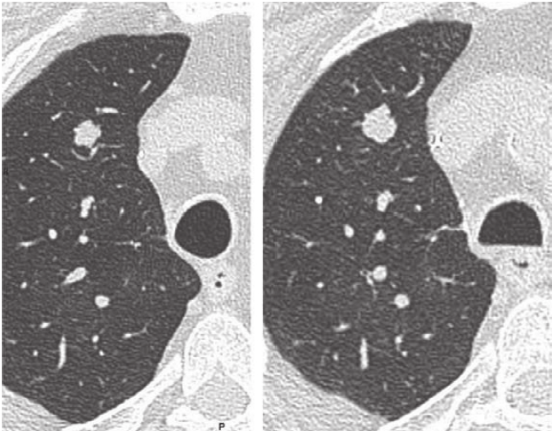

疑似转移的肺结节。左、呼气相,右肺上叶结节显示模糊,无法区分结节。右、吸气相,可以更好地区分单个结节。

孤立性肺结节。在吸气 (左) 和呼气 (右) 时显示右肺上叶有一个孤立性肺结节。结节在吸气和呼气之间的大小和形态都发生了变化,在吸气时为10.9mm X 9.3mm,在呼气时为12.3mm X 12.2mm。气管形状的差异可区分吸气和呼气。